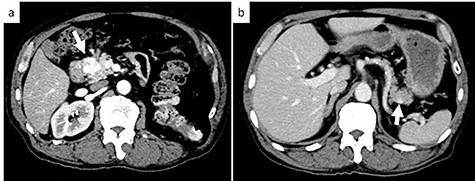

Subsequent contrast CT revealed two contrast-enhanced nodules in the pancreas head and tail (Fig. 2) showing that the tumor which caused the bleeding had a reduced uptake of contrast agent. Esophagogastroduodenoscopy showed a submucosal tumor in the descending part of the duodenum. Positron emission tomography-CT revealed a lesion with weak fluorodeoxyglucose uptake at the pancreas head (maximum standardized uptake value: 2.1). There were no lesions with fluorodeoxyglucose uptake in the tail of the pancreas or other organs.

Axial contrast-enhanced CT images; (a) CT showing a 25-mm well-defined hypervascular heterogeneous lesion in the pancreas head; (b) CT showing a 9-mm well-defined hypervascular heterogeneous lesion in the pancreas tail. White arrows indicate the tumor in the pancreas head and tail.